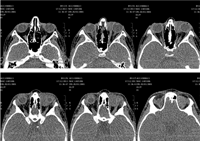

La tomografía computerizada (TC) de órbita (

Figura 1 y

Figura 2) evidenciaba una lesión ocupante de espacio de densidad de partes blandas de 3 centímetros de diámetro localizada a nivel superomedial de la órbita izquierda y que desplazaba el globo ocular anterolateralmente, así como al recto interno y el recto-oblicuo superior. No se apreciaban lesiones óseas, ni afectación de senos paranasales ni frontales.

Figura 1. TC órbita (axial).